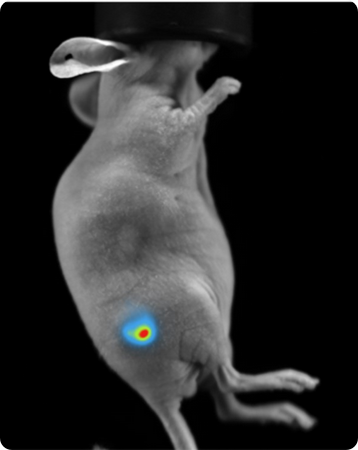

Bioluminescence imaging

Luciferase-expressing or secreting molecules in the target tissue can be found via bioluminescence imaging.

Subcutaneous tumor expressing firefly luciferase. Image Credit: Scintica Instrumentation Inc